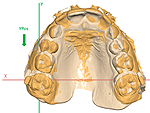

Three-Dimensional Analysis of Posterior Mandibular Displacement in Rats. Lyros I, Ferdianakis E, Halazonetis D, Lykogeorgos T, Alexiou A, Alexiou K-E, Georgaki M, Vardas E, Yfanti Z, Tsolakis AI. Vet Sci 2022;9,144. doi: 10.3390/vetsci9030144. PMID: 35324872.